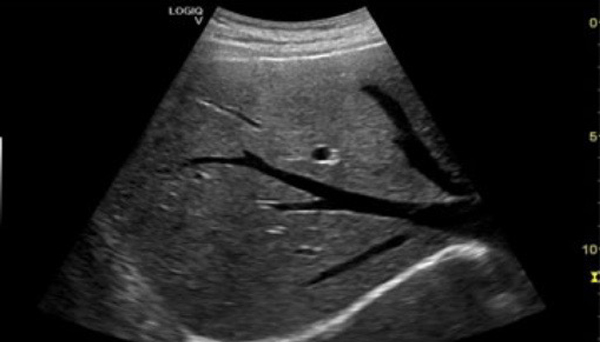

General Abdominal Sonography

General abdominal sonography, commonly known as an abdominal ultrasound, is a non-invasive imaging technique that uses high-frequency sound waves to create detailed images of the organs and structures within the abdomen.

This procedure is essential for diagnosing a variety of conditions affecting the liver, gallbladder, pancreas, kidneys, and other abdominal organs. The benefits of abdominal sonography include its safety (no radiation exposure), quick turnaround time, and ability to guide further diagnostic or therapeutic procedures.